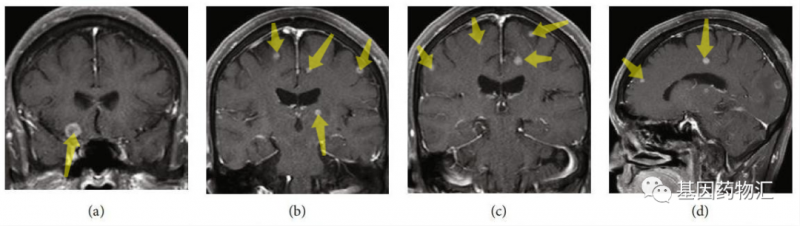

除了肺部的病灶,患者颅内的转移病灶也数量惊人,根据增强MRI的检查结果,病灶总共超过20个!属于非常典型的多发脑转移。

高龄、晚期、多发转移,这样的患者还有希望通过药物治疗达到缓解吗?事实上,在接受了仅仅5周的奥希替尼治疗之后,患者颅内的病灶,竟然完全消失了!

研究者据此指出,对于部分患者,尤其是将奥希替尼作为一线治疗方案的患者,脑部放疗完全可以推迟,甚至部分响应良好的患者根本不需要脑部放疗。

这说明,在某些特殊的情况下(比如患者可能很难耐受放疗,或颅内转移病灶数量过多等),可以考虑先使用奥希替尼治疗。如果患者对于药物的响应良好,很可能奥希替尼的治疗能够为脑部放疗提供条件,或者直接凭借药物治疗完全消除病灶。